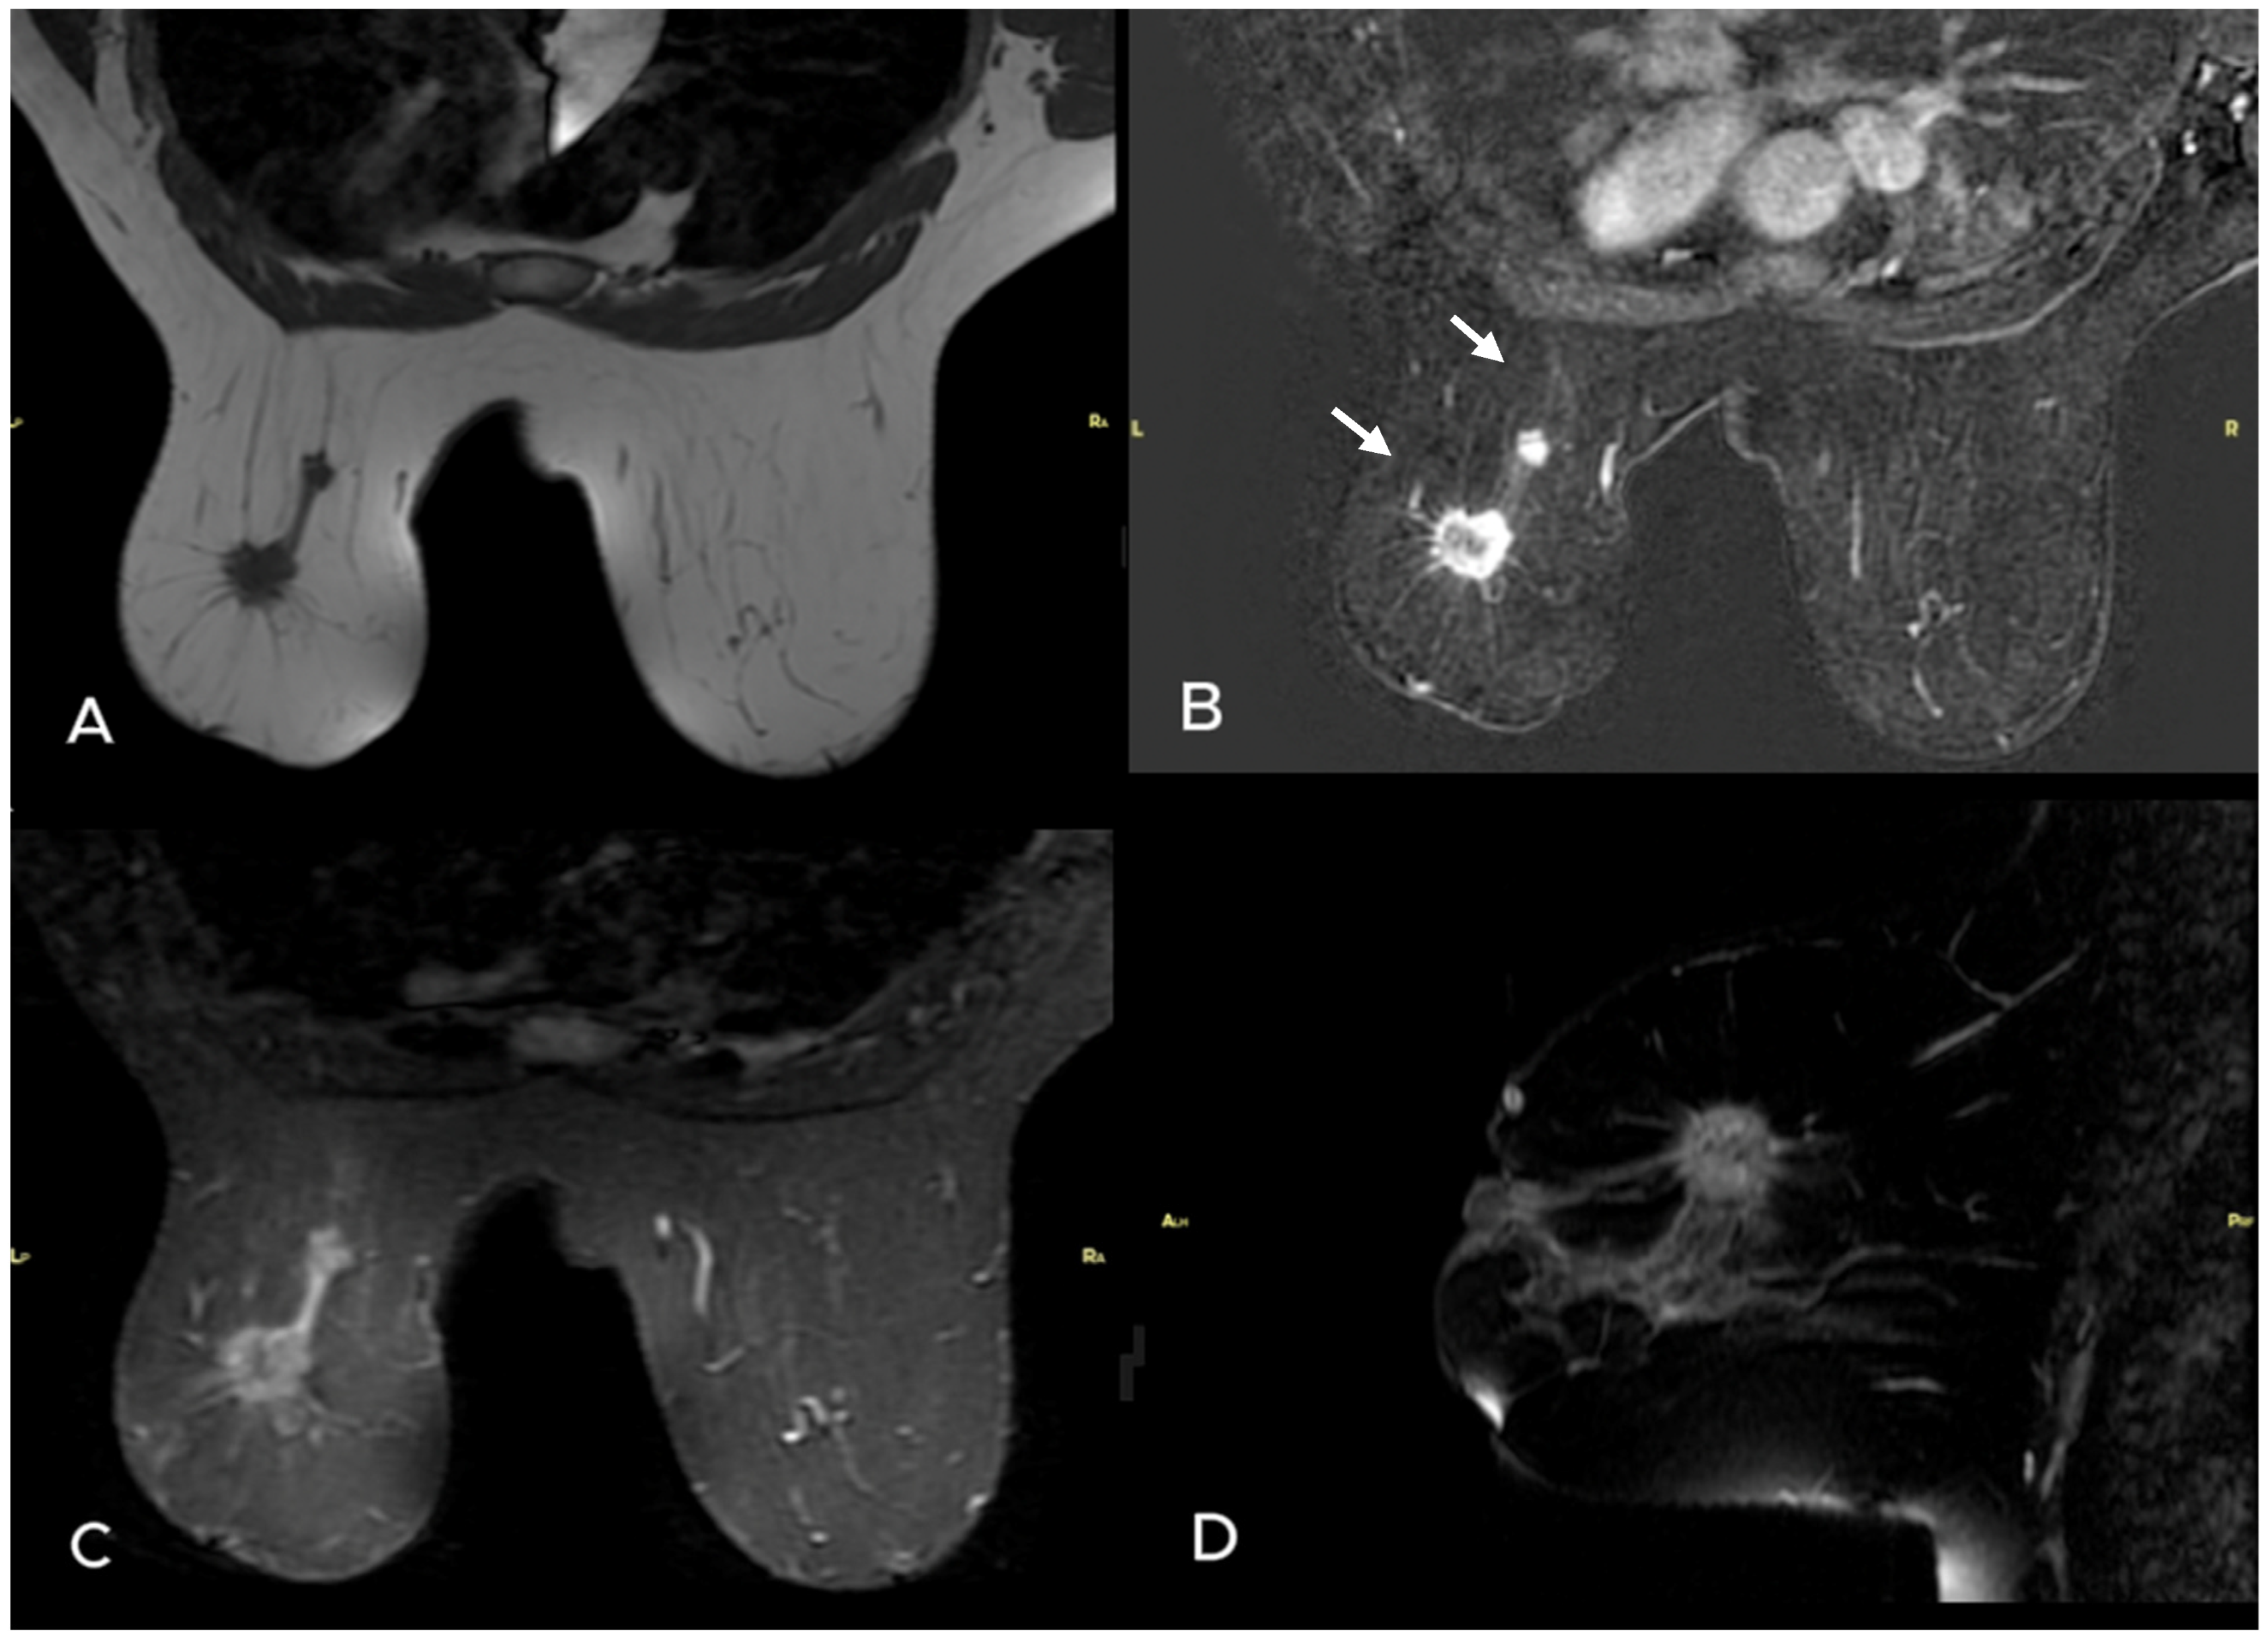

- Uematsu, T. Focal breast edema associated with malignancy on T2-weighted images of breast MRI: Peritumoral edema, prepectoral edema, and subcutaneous edema. Breast Cancer 2015, 22, 66–70. [Google Scholar] [CrossRef]

- Akdoğan Gemici, A.; Tokgoz Ozal, S.; Hocaoğlu, E.; Arslan, G.; Sen, E.; Altınay, S.; İnci, E. Relation of peritumoral, prepectoral and diffuse edema with histopathologic findings of breast cancer in preoperative 3T magnetic resonance imaging. J. Surg. Med. 2019, 3, 49–53. [Google Scholar]